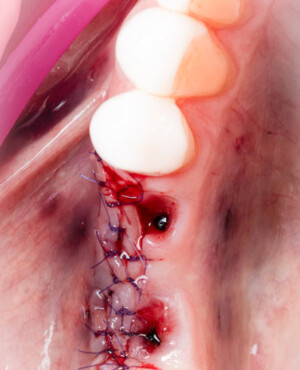

Procesul de refacere osoasă este complex, însă, simplificat, se bazează pe faptul că osul adăugat se integrează treptat, fiind înlocuit parțial cu os natural, oferind astfel suportul necesar implantului.

Un element esențial în procedura de aditie osoasă este utilizarea membranelor biologice, care izolează materialul osos de țesuturile moi (gingie) pe durata procesului de vindecare. Cele mai recomandate sunt membranele resorbabile din colagen sau pericard.